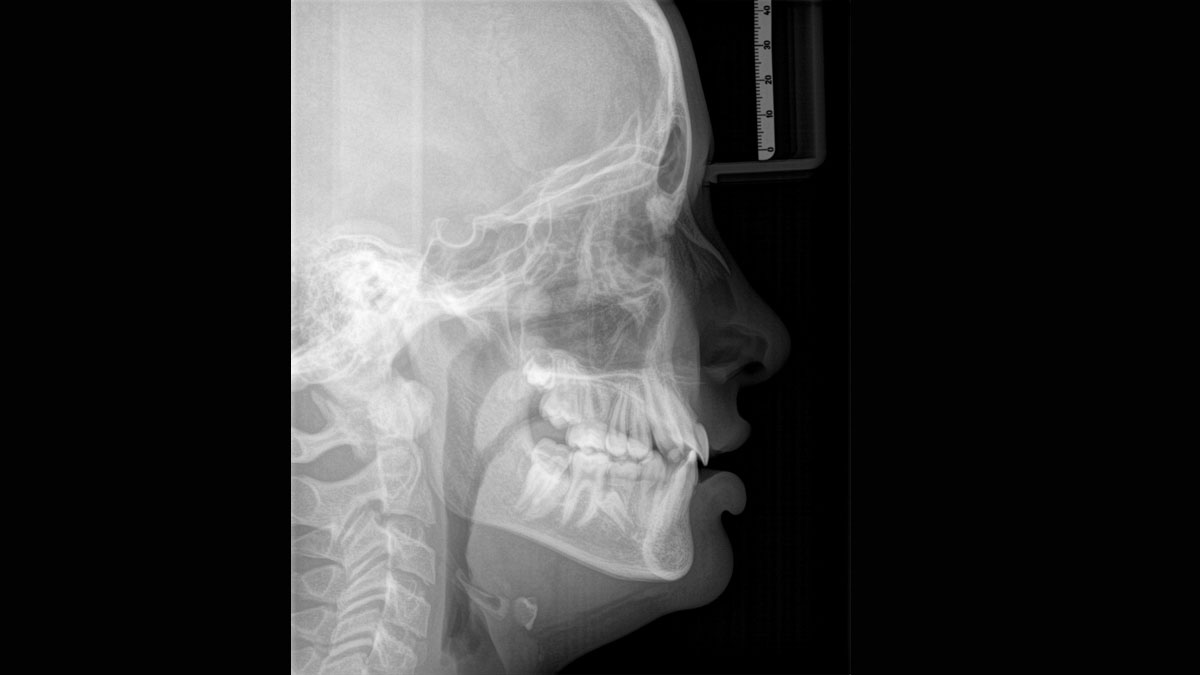

El equipo de radiología 2D/3D de alta calidad con una amplia gama de servicios para cada clínica. Ya sea como un dispositivo puramente 2D o como un módulo 3D, el Orthophos S es un socio confiable y está optimizado para las tareas diarias. Su sensor CsI Plus con función de autofoco garantiza imágenes claras, incluso en casos anatómicamente difíciles. El posicionamiento automático del paciente junto con el bloque de mordida oclusal patentado permite un posicionamiento del paciente fácil y que ahorra tiempo. Para su uso en ortodoncia, la Orthophos S también está disponible con un brazo cefalométrico opcional. Y como para Dentsply Sirona es importante estar preparado para el futuro, el brazo cefalométrico se puede reacondicionar en cualquier momento.

Incluso en casos anatómicamente difíciles con el sensor 2D CsI con función de autofoco

El enfoque correcto es crucial para excelentes radiografías panorámicas. Con la función de autofoco, usted recibirá automáticamente una imagen con la mejor nitidez posible en foco. Los dispositivos de radiología de Dentsply Sirona toman varios miles de imágenes individuales en un ciclo e identifican automáticamente las áreas donde la mandíbula está posicionada de manera óptima. Luego, sin ningún paso manual adicional, estas imágenes se muestran en una nítida imagen final.

Solo algunas partes de la imagen están en foco, mientras que otras áreas están borrosas.

El sistema detecta las áreas relevantes a partir de varios miles de imágenes individuales en un ciclo e identifica automáticamente las áreas donde la mandíbula está posicionada de manera óptima.

Imágenes nítidas.